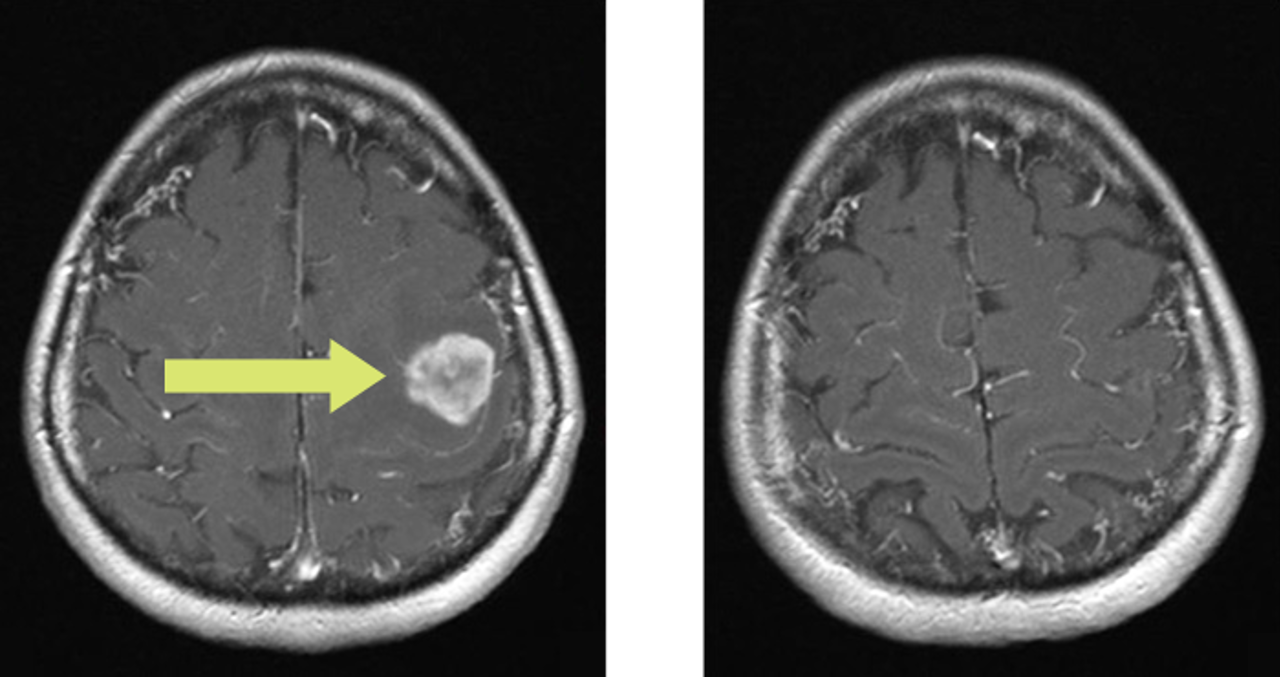

Слева: У пациентки с раком молочной железы был выявлен одиночный метастаз в головном мозге, окружённый выраженным отёком. Опухоль располагалась в критически важной центральной зоне, отвечающей, среди прочего, за двигательные функции.

Справа: После радиохирургического лечения с использованием системы CyberKnife метастаз был полностью устранён. Уже через 22 месяца после терапии (длительность процедуры — всего 25 минут) на МРТ нет признаков опухоли.

Также полностью исчез отёк, ранее вызывавший опасное давление на мозговые структуры.